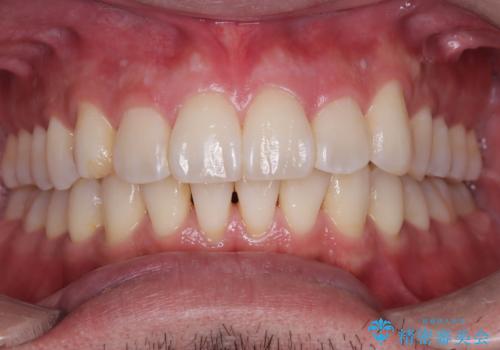

前歯をきれいにしたい オールセラミッククラウンにによる補綴